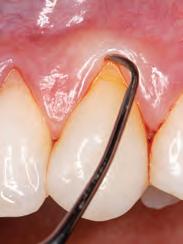

Dental matrix systems: Several commercially available stock matrices are available to the dentist (e.g. Bioclear, Unica and others) to facilitate the placement of composite resins. These matrices (Fig. 3) are appropriate for almost any size and type of restoration.28 They are inserted under dental dam isolation and positioned between the rubber dam and the tooth.29 The rubber dam acts as a rubber band around the tooth, sealing it against the tooth, thus preventing excess material from penetrating the sulcus and creating ledges.28 Additionally, since the composite is polymerized against a very smooth surface, minimal or non-finishing is typically required in the proximal areas. Leaving this highly smooth surface prevents minimal plaque and calculus accumulation.29

Monochromatic materials are used with these matrices and involve the injection of a flowable (no light-curing) followed by a conventional viscosity that extrudes the flowable. This process aids in the insertion of material and elimination of voids.25 The authors prefer heated composites, which can further help their insertion. If a polychromatic restoration is desired, a cut-back approach (also called the window technique) can be employed, involving the removal of some facial composite and its replacement with other opacities and stains to produce halos and incisal translucency.28 These matrices provide suitable proximal contour, but attention should be paid to plastic matrices that require thickness for stiffness, potentially resulting in open contacts. The facial

and lingual surfaces still need contouring and polishing to replicate anatomical contours and blending, which can be considered a disadvantage of this method.

The Bioclear matrices deserve special attention since they are presented as an excellent alternative for closing black triangles and closing diastemas. These matrices prevent any gingival excess in the interproximal area, which is difficult to access for removal and finishing, but instead extrude any excess onto the facial or lingual, where contouring and polishing are more accessible.28 The instruments required for this technique are the same as the free-hand technique with the addition of the matrices.25 When used for black triangles and diastema closures, the clinician can establish the optimal curvature for closing gingival embrasures.29 The Bioclear black triangle kit comes with a colour-coded gauge inserted into the black triangle or diastema space and then corresponding with colours at the top of the matrix.28 This allows the clinician to choose the appropriate size and contour matrix.28,29 In the author’s experience, selecting one size larger matrix than the corresponding colour from the colour-coded gauge is better. The matrices are offered in two sizes (big and small) and four curvatures (red, yellow, green, blue), allowing the operator to treat the entire anterior sextant, from canine to canine, in both upper and lower arches.28 This results in robust and esthetically acceptable outcomes.29 Patients with substantial midline diastemas often lack interdental papilla, influenced by the distance between the interdental contact point and the alveolar bone crest.29,30

A previous study indicated that when this measurement is 5 mm or less, the interdental papilla is present in nearly 100% of cases.30 However, as this distance increases, the likelihood of papilla presence decreases.30,31(Fig. 4). To address this, rubber dam isolation is crucial for preventing moisture contamination and facilitating effective gingival retraction.29 This retraction enhances access to the cervical area, allowing the addition of composite material in spaces previously occupied by gingival tissue.25,29 This process helps prevent the formation of non-esthetic black triangles and achieves a more aesthetically pleasing result.28

Fig. 3a: A Bioclear gauge measures the black triangle between the tooth, the upper right canine, and the lateral incisor.

Fig. 3b: Bioclear matrix tryin. Note using a larger matrix than recommended by gauge.

Fig. 3c: Flowable composite injection. Fig. 3d: Post-operative result.